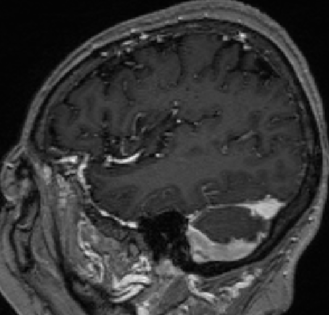

2013-8-2 MRI

2013-8-2 CT

腰穿脑压240